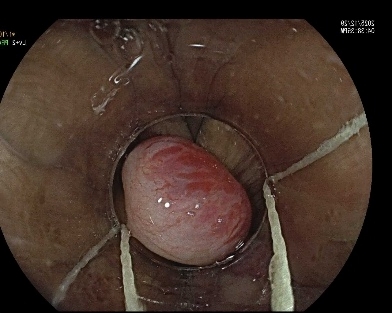

痔疮作为肛肠科常见疾病,传统治疗方法包括药物保守治疗或外科手术,但存在复发率高、创伤大、恢复慢等痛点。孔德润团队采用“内镜下硬化剂注射”技术,通过高清电子内镜的精准定位,针对出血风险较高的区域注射泡沫硬化剂,形成机械性封闭,从根源上降低复发风险。内镜就像医生的‘第三只眼’,不仅能直视黏膜表面,还能观察痔核结构,实现“指哪打哪“的精准操作。